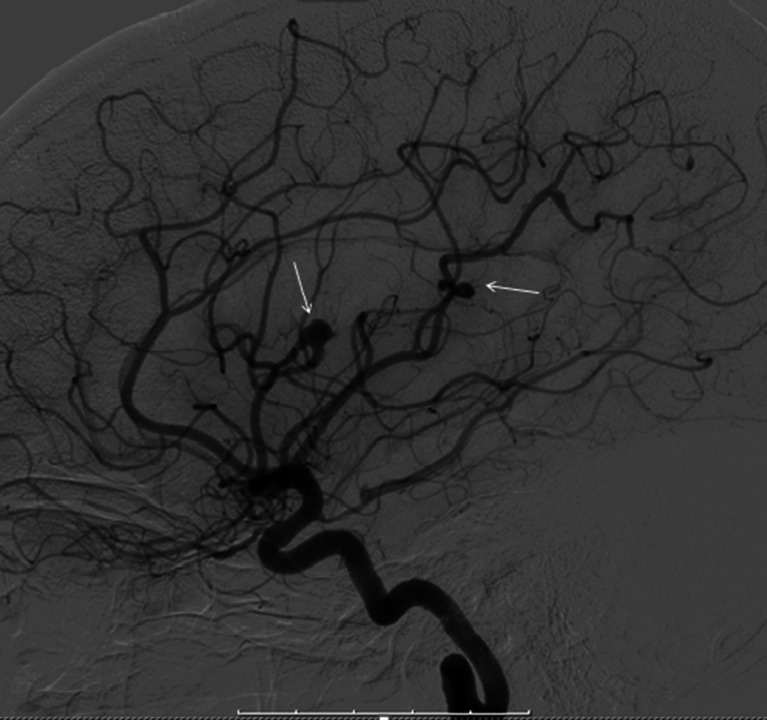

One year later she presented to the emergency department with complaints of sensory loss in her tongue and face, and word finding difficulty. These complaints had existed for 1 week and had already partly resolved. Neurological examination was without further abnormalities. A CT scan showed six haemorrhagic lesions in the right cerebral hemisphere. A following MRI scan of the brain also showed multiple haemorrhagic lesions and was suggestive for cerebral micro-aneurysms (Fig. 2). A transthoracic echocardiogram showed no signs of recurrence of the myxoma. There were also no indications of vasculitis. Cerebral angiography showed micro-aneurysms in the right middle cerebral artery (Fig. 3). The diagnosis myxoma-related cerebral micro-aneurysms was made. These findings and the management options were discussed with the department of neurosurgery and it was decided to treat her conservatively. Up till now she is doing relatively well. Her complaints have largely resolved. She is being treated medically for epileptic seizures and occasionally she suffers from headaches and tingling of her tongue. A follow-up cerebral MRI showed no progression of the lesions.

Fig. 3.

Cerebral angiography showing aneurysms in the left middle cerebral artery (arrows)